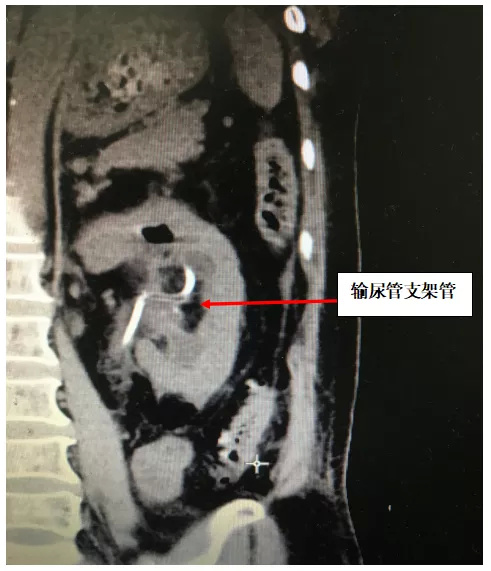

两周后,由俞国锋主任率领的结石团队再次为患者行2期输尿管软镜+经皮肾镜、双镜联合取石术,将左肾内残余结石完全清除干净,碎石、取石一气呵成。术后第1天复查CT,结石全部清理干净肾脏无出血,术后第3天患者顺利出院。

术后CT